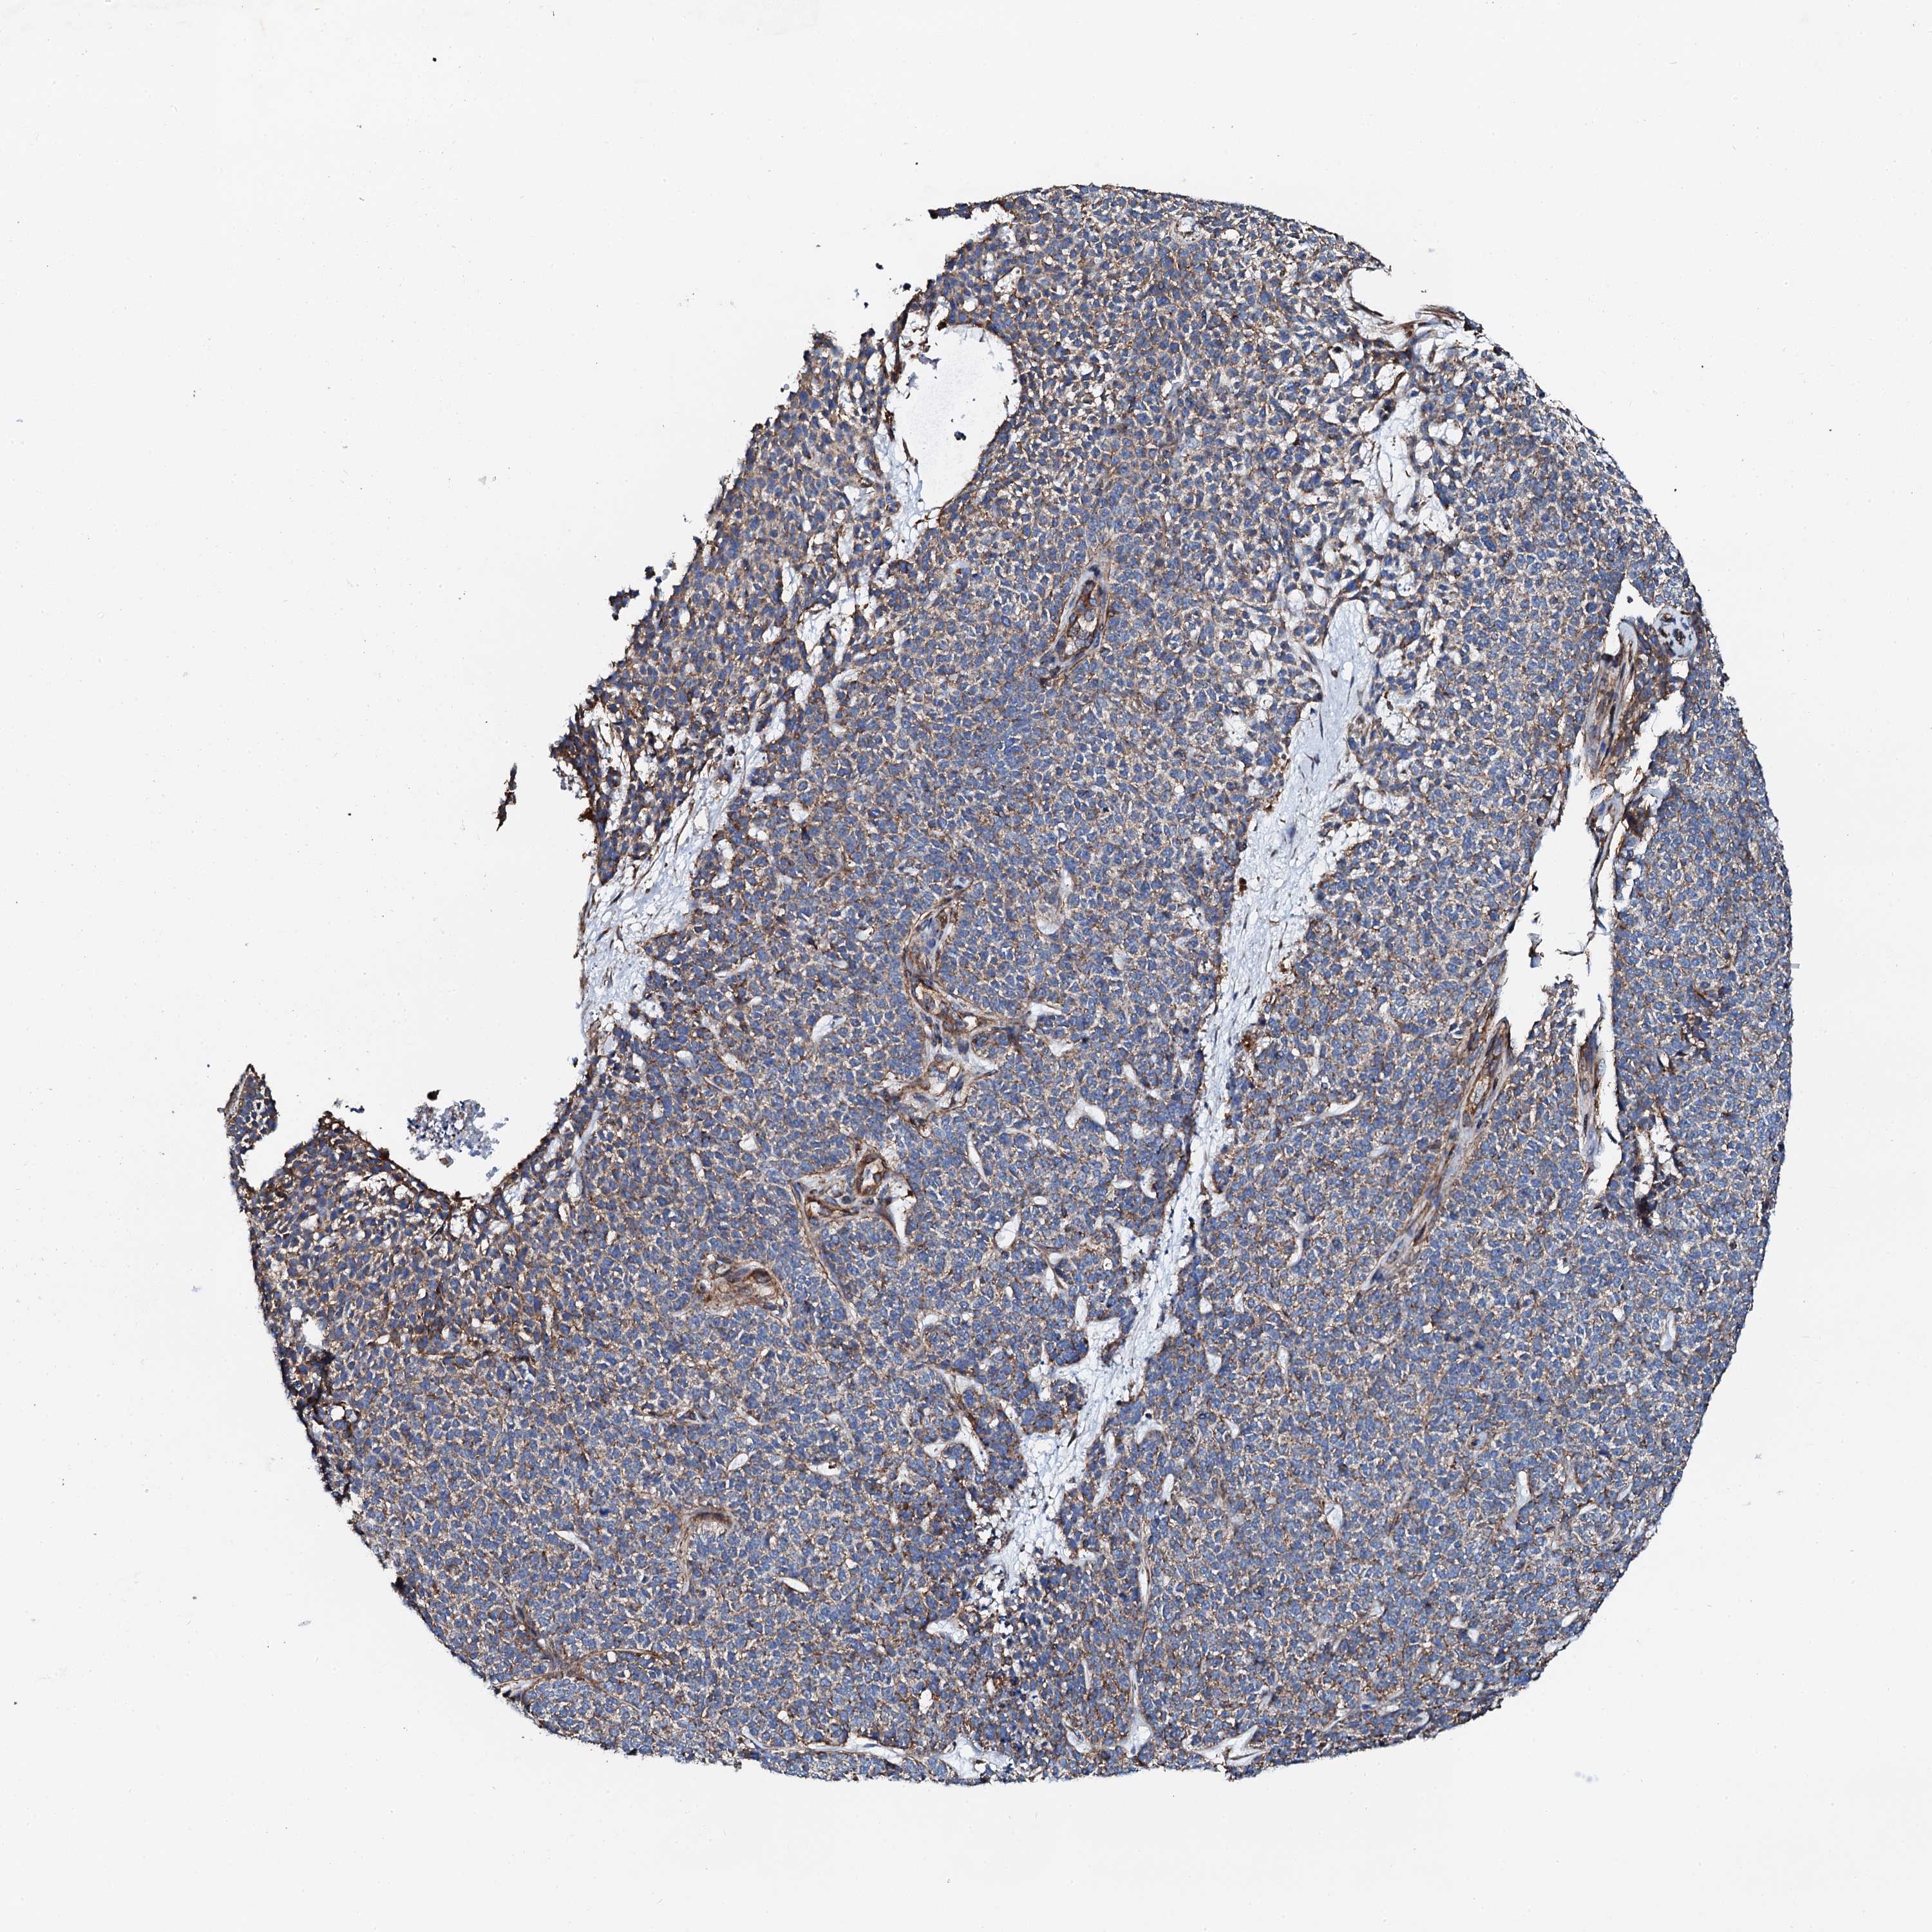

SKIN CANCER - Protein expressioni

A mouse-over function shows sample information and annotation data. Click on an image to view it in a full screen mode. Samples can be filtered based on level of antibody staining by selecting one or several of the following categories: high, medium, low and not detected. The assay and annotation is described here.

Antibody stainingi

Antibody staining in the annotated cell types in the current human tissue is reported as not detected, low, medium, or high, based on conventional immunohistochemistry profiling in selected tissues. This score is based on the combination of the staining intensity and fraction of stained cells.

Each image is clickable and will lead to virtual microscopy that enables deeper exploration of all samples and also displays staining intensity scores, fraction scores and subcellular localization as well as patient and tissue information for each sample.

Antibody HPA039129

Antibody HPA050570

Staining

High

Medium

Low

Not detected

Intensity

Strong

Moderate

Weak

Negative

Quantity

>75%

75%-25%

<25%

None

Location

Nuclear

Cytoplasmic/membranous

Cytoplasmic/membranous,nuclear

Basal cell carcinoma

Squamous cell carcinoma, NOS